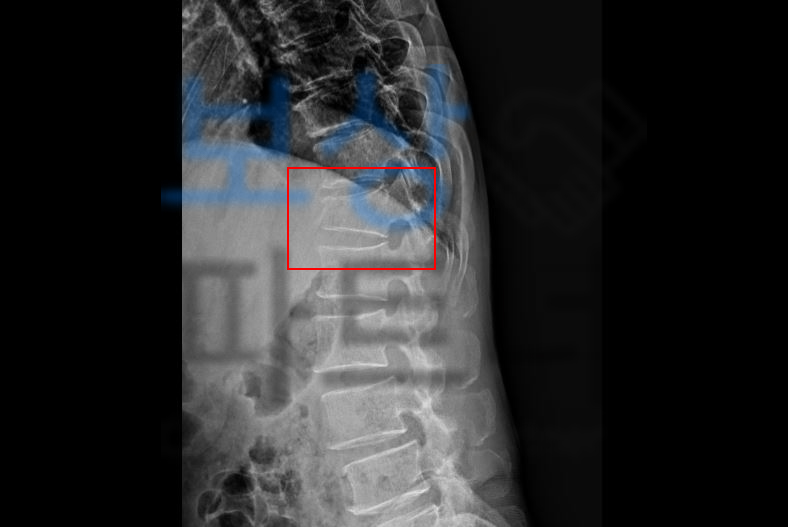

산에서 벌목 일을 하다 나무에 허리를 맞아 넘어지신 권@@님… 급히 병원으로 내원하여 정밀검사를 받아보니.. 흉추12번 골절 S22090

엑스레이 권@@님 척추체의 압박률을 보던 주치의는 척추성형술 즉 골시멘트 술을 권하였고